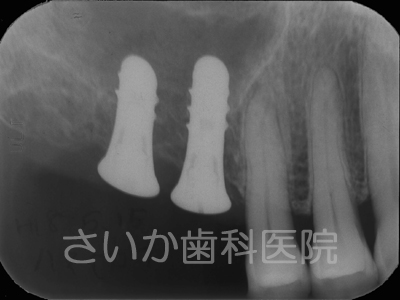

上の奥歯2本を歯周病で失ったため,骨が吸収しています。ヒトの上あご内部には「上顎洞」と呼ばれる空洞があるため,骨の厚みは矢印で示した厚みしかありません(上図右)。

「ソケットリフト」という治療法は「上顎洞」の底面部にインプラントを粘膜を破らないように突きだしてやる方法です。

手術後,しばらくしますと突きだしたインプラント周囲には骨が自然に出来てきます。骨の再生に人工的な物を使用せず,移植も必要としないため,患者様への負担は少ない治療法のひとつです。下の写真はインプラントを入れて5年が経過した写真です(パノラマレントゲンのため,画質が粗くなっています)。